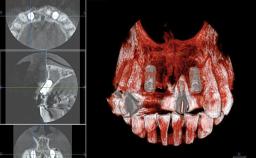

A 45-year-old woman was referred for management of an infection associated with two implant-supported crowns replacing the maxillary central incisors. Two tissue-level implants had been placed and restored with cemented single metal-ceramic crowns in those sites 4 years previously. The patient presented with a draining sinus (i.e. a pathological duct from an abscess cavity to a surface) 3 mm from the midfacial peri-implant mucosal margin of the maxillary right implant crown. She was in good general health, did not smoke, showed a good oral hygiene status, and had no history of periodontal disease. The implants were well positioned. While the patient was very satisfied with the appearance of her crowns, she had noted that the peri-implant soft tissue had receded since their insertion and was concerned about the possibility of further recession.